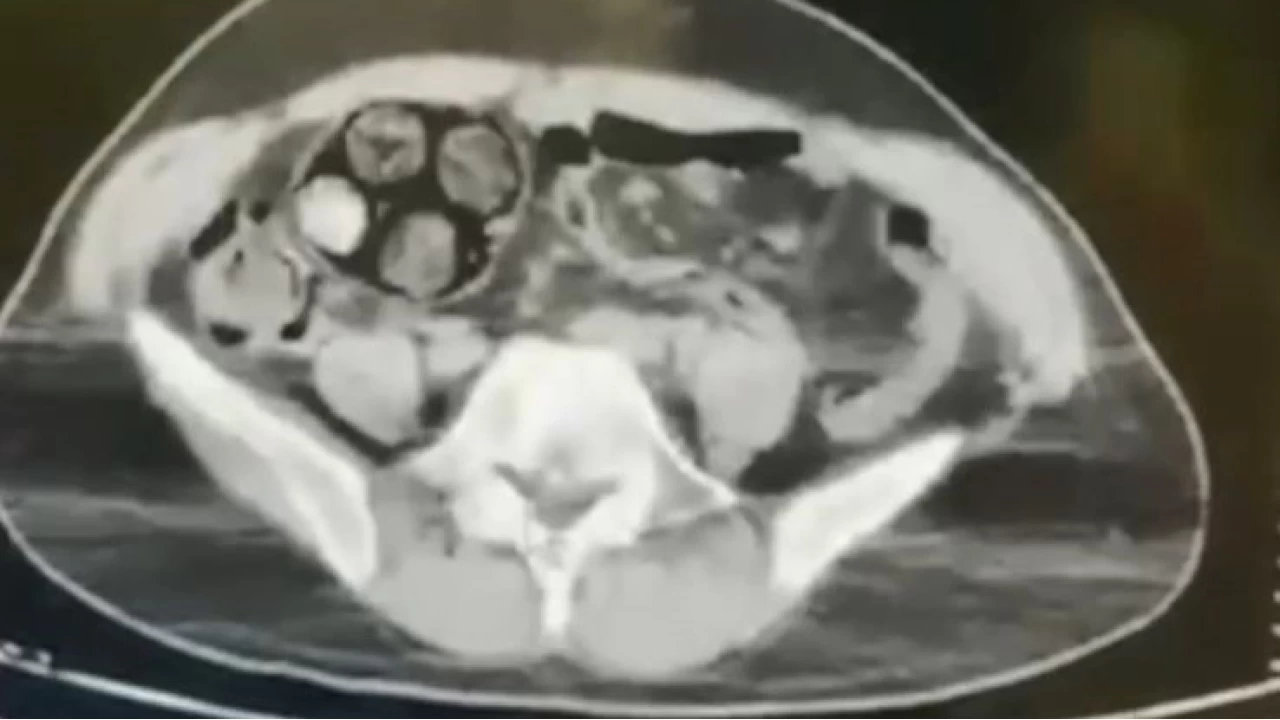

Çekilen tomografi sonucu zanlının bağırsaklarında 10 paket tespit edildi. Cerrahi müdahale ile çıkarılan paketlerin içinde toplamda 350 gram metamfetamin maddesi olduğu belirlendi. Gözaltına alınan İranlı zanlı hastanede müşahede altına alınırken, olayla ilgili soruşturma başlatıldı.